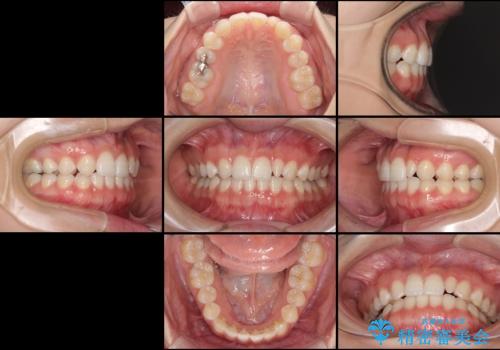

海外転居前に気になる前歯を整えたい 上下前歯の部分矯正

- 1年後に海外に転居するため、気になる前歯を矯正治療で整えたいとのことで来院された患者様です。

下顎は叢生が強かったため、奥歯までワイヤーを装着し、上顎は前歯の一部のみ気になっていたので、その部分にだけワイヤー装置を装着することとしました。